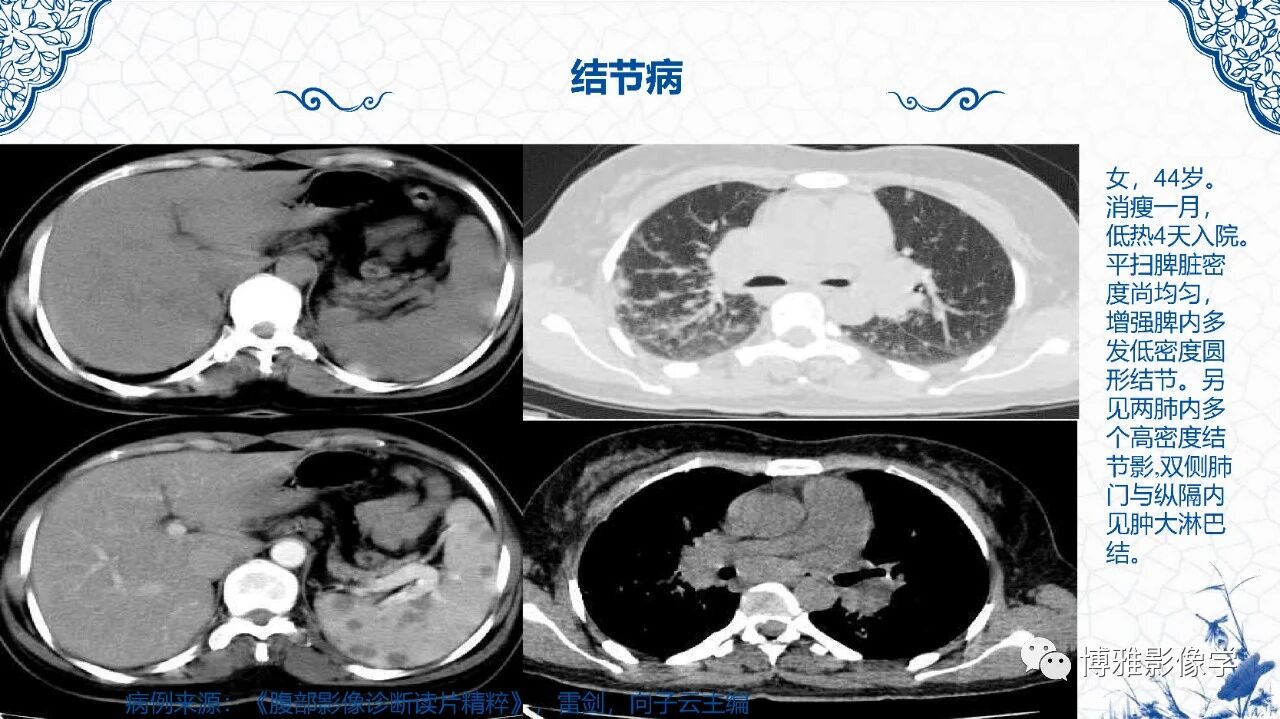

脾脏非肿瘤影像诊断